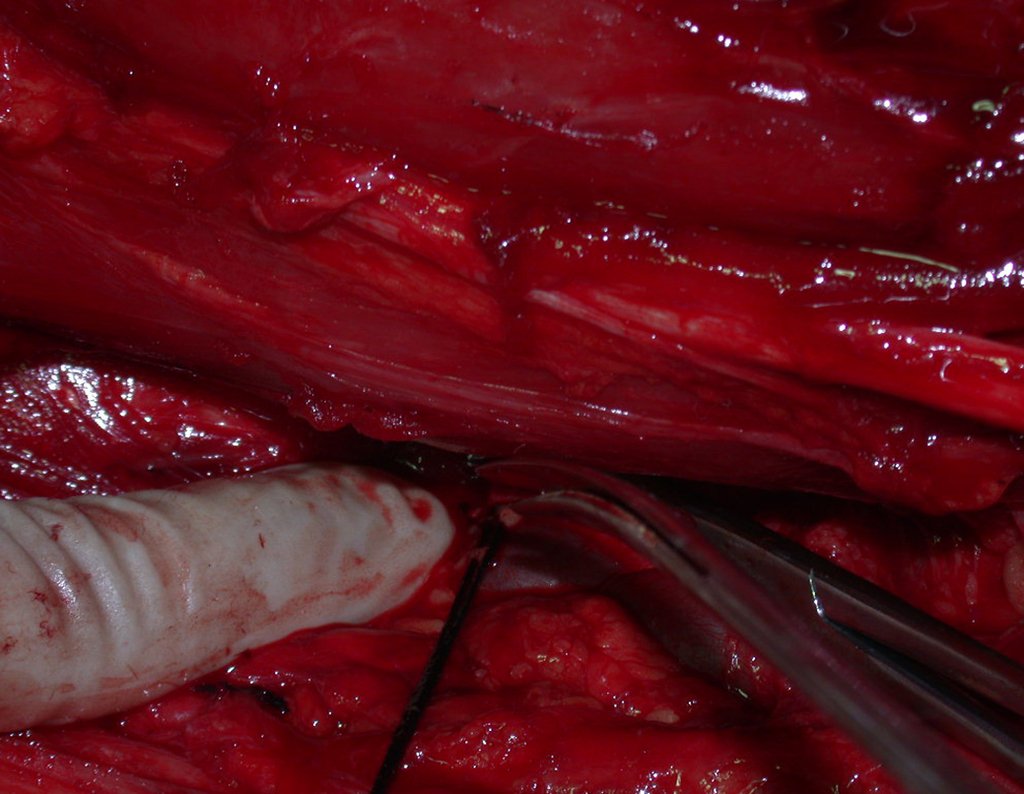

- Ressecção

- Uma incisão ampla foi realizada para permitir a ressecção com margem de segurança.

- Dissecção cuidadosa com hemostasia, seccionando e amarrando os segmentos musculares.

- Isolamento do nervo femoral e dissecção dos vasos ilíacos.

- Ligadura da veia e artéria ilíacas internas.

- Dissecção da região sacro ilíaca e preparação para osteotomia.

- Ressecção do tendão do músculo psoas e remoção do músculo ilíaco junto com a peça cirúrgica.

- Ressecção em bloco da hemipelve esquerda e revisão da hemostasia.